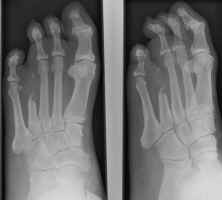

The images to the left show a proximal

transmetatarsal amputation through digits 4 and 5.